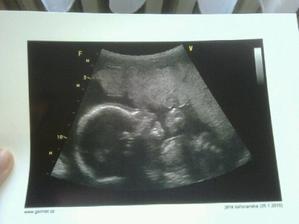

26.01.2010 - kontrola v Gennetu u Dr. Hynka - manžílek zjistil, že místo holčičky se dočká chlapečka, takže teď mu tvář zdobí tak blaženej úsměv :D Je pravda, že mě to trochu zaskočilo, ale už se nemůžem dočkat. .. Takže Ondrášku, ještě 132dní a budeš u nás 🙂 Jinak všechno v pořádku - srdíčko, velikost, váha 320g, stáří 21tt,.... Jinak se máme fajn, už se těšíme na první pohyby 🙂 Další kontrola je na Mělníku za týden ....------------------------------------------------------------------------3. 2. 2010 – desátá kontrola –(podle PM 22+1), AS+, HC (obvod hlavičky) 199 mm/21+6, FAC 171 mm/21+6, BPD 53 mm/22+1, FL (délka stehenní kosti) 37 mm/21+3, váha 464g, obličej bez roštěpu, 4 končetiny, žaludek +, srdce 4 oddíly, bránice +, moč. měchýř naplněn, ledviny + bez dilatace. – No takže vše v pořádku... p.Dr. potvrdila střapeček – takže jsi náš malej chlapeček . Zatím máš asi spoustu místečka v břiše, jelikož tvoje pohyby stále necítím. Občas večer u TV jako by mi něco bublalo v podbřišku, ale kdo ví. Taky máme prodlouženou neschopenku, takže spolu budeme doma v teplíčku a klídku. Zítra teda musím do laborky s močí a krví – jelikož máme bílkovinu v moči, ale snad nic vážného. Další kontrola 3.3.2010. ----------------------------------------------------------------------------------------------------------------